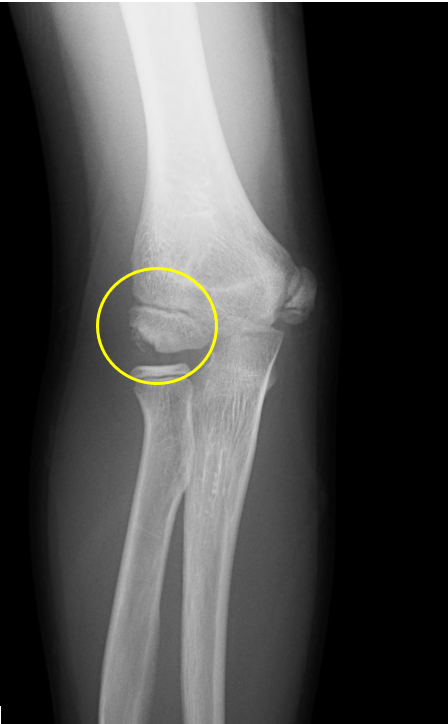

肘の離断性骨軟骨炎(以下:OCD:osteochondritis dissecans)は上腕骨小頭という部位に好発することが多いです。

OCDは成長期の代表的なスポーツ障害であり、野球などといった投球・投擲動作を行うスポーツ選手で投球側に発生することが多いです。大半は10-12歳で発症し成長期における有病率は2-3%と頻度は少ないが進行するとスポーツにみならず、日常生活お支障をきたすことが多い怪我です。そのため、早期発見・早期治療が重要となります。

一般的にレントゲンによる分類が用いられ、初期・進行期・終末期に分けられます。

OCDを発見するにはレントゲンや超音波検査で上腕骨小頭軟骨下骨の状態を観察します。

軟骨下骨の不整像が軽微か不明の場合はMRI検査を行いOCDの確定診断を行います。

2024年5月、当院受診。レントゲン撮影をして離断性骨軟骨炎と診断されてリハビリ開始。